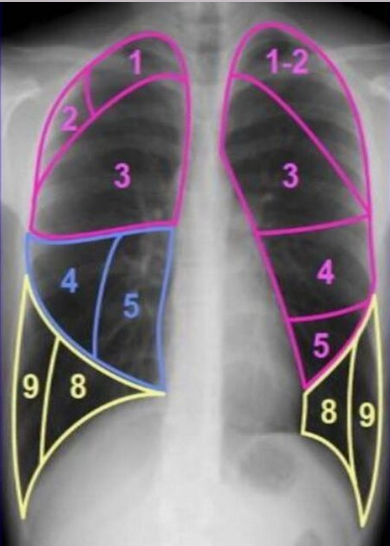

Часть легкого, вентилируемая сегментарным бронхом. Снабжается кровью через сегментарную легочную артерию, отток крови осуществляется в сегментарную вену между двумя соседними сегментами. В доле легкого может быть от 2 до 5 сегментов.

Отдельные сегменты в норме не разделены висцеральной плеврой на рентгенограммах и КТ-срезах. Об их границах и расположении косвенно позволяют судить междолевые щели (см.), сегментарные бронхи и артерии. Относительно редко можно видеть дополнительные сегментарные щели, которые также помогают разграничить сегменты.